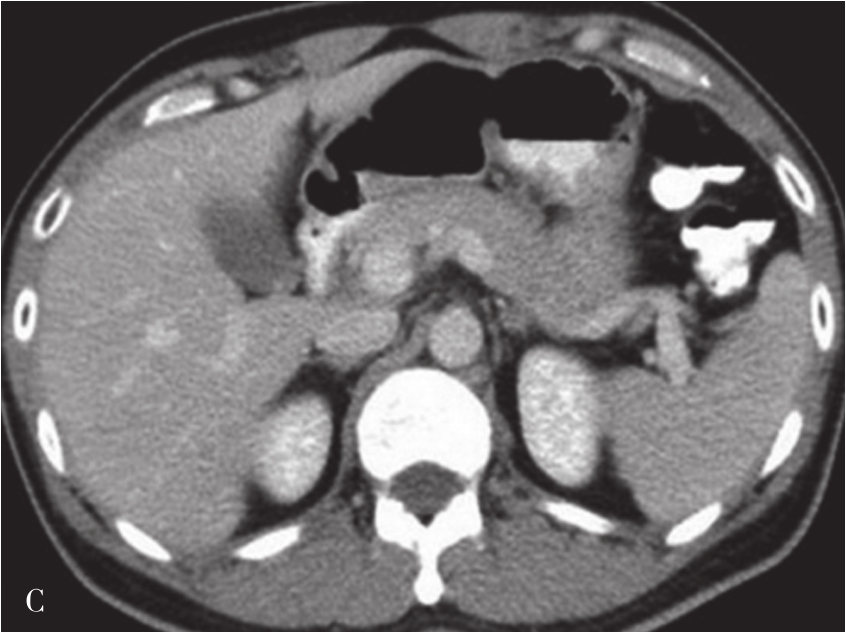

(1)肝脏大小和形态:

肝脏内的脂肪浸润及肝硬化再生结节使得肝脏体积增大,中、晚期肝硬化由于纤维组织增生又使得肝脏体积缩小,以肝裂增宽为主,胆囊窝扩大,肝脏表面呈波浪状改变。通常肝右叶缩小明显,而尾状叶及左叶则可出现代偿性的增大(图5-21-37)。

图5-21-37 CT增强扫描门静脉期图像

可见肝脏形态异常,肝裂增宽,肝叶比例失调,肝脏体积缩小,肝包膜增厚,肝脏边缘呈波浪状改变,门静脉主干管径增宽,直径约1.8cm。脾脏体积明显增大,脾静脉增粗,同时可见食管胃底静脉曲张(箭头),肝周、脾周可见弧形液性密度影